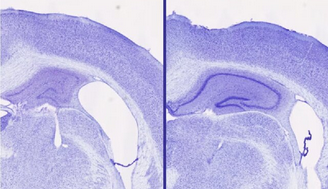

موشهای مصرفکننده «لمبورکسانت» 30 تا 40 درصد حجم مغز بیشتری در هیپوکامپ (ناحیهای حیاتی برای عملکرد شناختی سالم) نسبت به حیواناتی که زولپیدم مصرف میکردند، داشتند. حتی اگر هر دو گروه تقریباً به یک میزان خواب داشتند. از دست دادن حجم مغز، نشانهای از تخریب عصبی است.